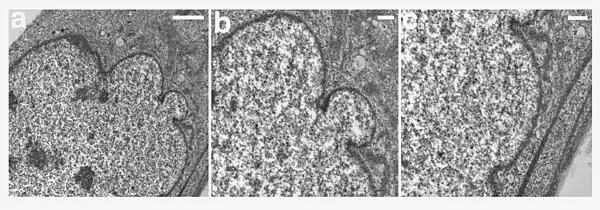

| A young girl with progeria (left). A healthy cell nucleus (right, top) and a progeric cell nucleus (right, bottom). | |